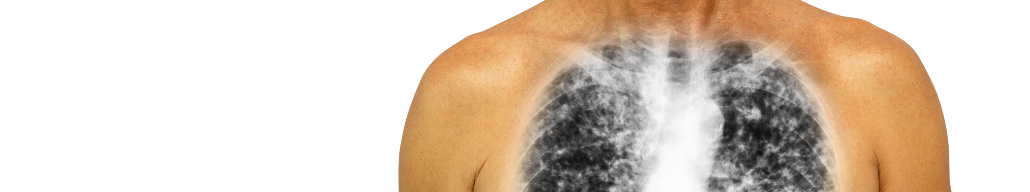

Постковидные изменения в легких - как выявлять и что делать?

В последнее время в печати появляется все больше материалов, посвященных постковидным изменениям в разных органах. Сегодня предлагаем вам, уважаемые коллеги, ознакомиться с кратким переводом статьи зарубежных авторов, посвященной персистирующей постковидной интерстициальной болезни легких1.

Во введении авторы отмечают, что естественное течение процесса восстановления после перенесенного тяжелого острого респираторного синдрома, вызванного коронавирусом (SARS-CoV-2), остается малоизученным. Поскольку ранее был описан фиброз легочной ткани со стойким нарушением функции легких как особенность пациентов, выздоравливающих после вирусной инфекции, вызванной коронавирусами, закономерно предположить, что рано начатое лечение способно изменить течение заболевания, потенциально предотвращая необратимые нарушения.

Цель исследования: определить частоту и описать прогрессирование стойкого воспалительного интерстициального заболевания легких (ILD) после SARS-CoV-2 при лечении преднизолоном.

Методы: авторами был использован структурированный протокол оценки последствий пневмонита, вызванного SARS-CoV-2. Восемьсот тридцать семь пациентов были опрошены по телефону через 4 недели после выписки. Пациенты с сохраняющимися симптомами проходили амбулаторное обследование в течение 6 недель – изменения в легких определялись с помощью компьютерной томографии. Тридцать пациентов с диагнозом стойких интерстициальных изменений легких были обследованы специалистами по интерстициальным заболеваниям легких, и по итогам им было предложено лечение.

Результаты: через 4 недели после выписки 39% (325/837) пациентов сообщили о сохраняющихся симптомах и были обследованы. Интерстициальное заболевание легких, преимущественно в виде пневмонии, со значительным нарушением функции легких наблюдалось у 35/837 выживших (4,8%). Тридцать из этих пациентов получали лечение коритикостероидами, что привело увеличению среднего показателя диффузионной способности легких после лечения на 31,6% (стандартное отклонение [SD] ± 27,6, Р < 0,001) и форсированной жизненной емкости на 9,6% (SD ± 13,0, Р = 0,014) со значительным симптоматическим и рентгенологическим улучшением. Осложнения лечения не были выявлены ни в одном случае.

Выводы: После пневмонита SARS-CoV-2 у части пациентов остаются как рентгенологические признаки воспалительного процесса в легких, так и стойкий функциональный дефицит. Раннее лечение кортикостероидами хорошо переносилось и сопровождалось быстрым и значительным улучшением. Эти предварительные данные должны послужить основой для дальнейшего изучения естественного течения изменений в легких и возможности лечения пациентов с персистирующей интерстициальной болезнью легких после инфекции SARS-CoV-2.